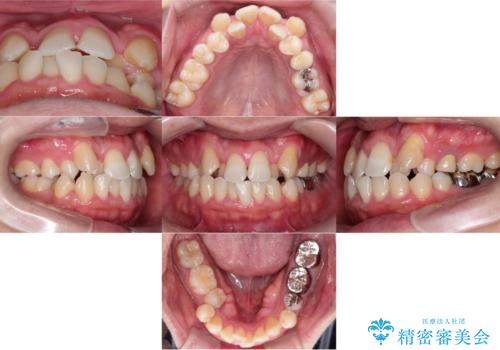

転位歯や埋伏歯などの難易度の高い抜歯矯正治療

【モニター】八重歯と正中を改善 ワイヤー装置の抜歯矯正